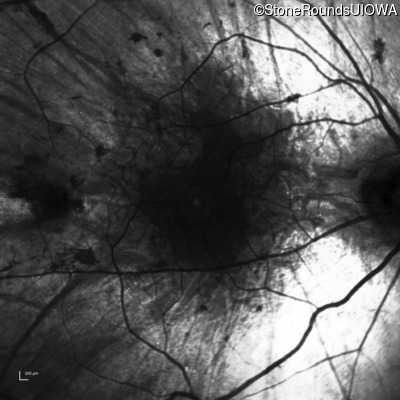

Infrared Fundus Photograph - Right - 20/25 -1

Exemplar

Infrared Fundus Photograph - Left - 20/30